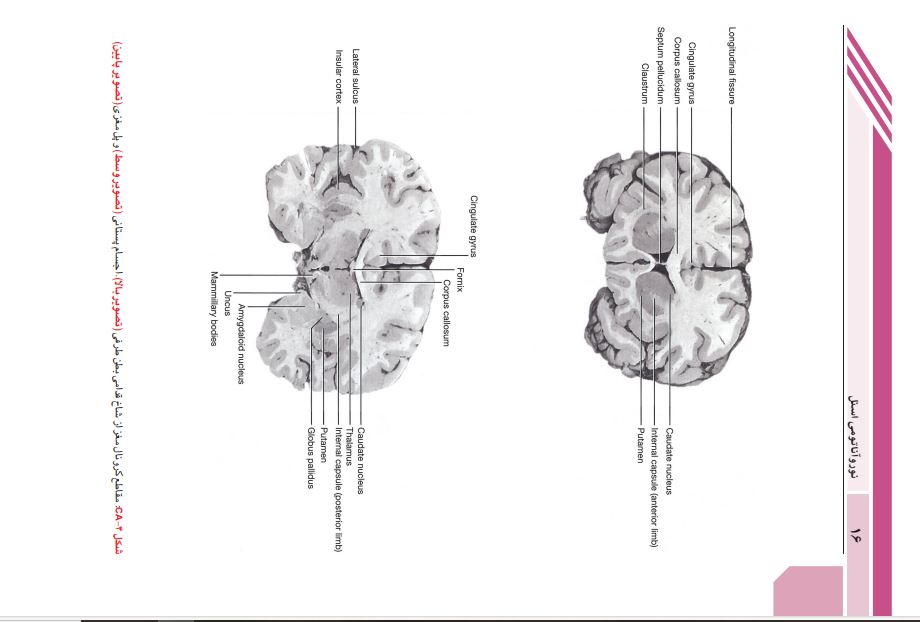

این کتاب ترجمه ی ویرایش نهم نوروآناتومی بالینی اسنل است.. این کتاب دربرگیرنده ی پایه ای ترین نکات علمی نوروآناتومی است که برای حرفه پزشکی ضروری است. در این ویرایش نویسنده ی کتاب تغییر یافته است. مطالب هر فصل مرور و ویرایش شده تا نکات نوروآناتومی به بهترین نحو ارائه شوند. تصاویر قبلی کتاب به روز شده و رنگ بندی آن ها تغییر یافته تا مطالب ارائه شده در هر تصویر گویاتر شوند.تصاویر MRI و میکروگراف های بافت شناسی با کیفیت بالا تهیه شده اند تا اطلاعات بصری دقیق تری ارائه دهند.

__فصل13:مخ